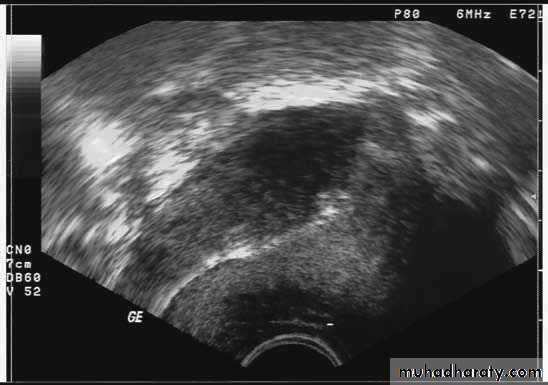

Ultrasound imaging

Copper IUD

LNG IUD